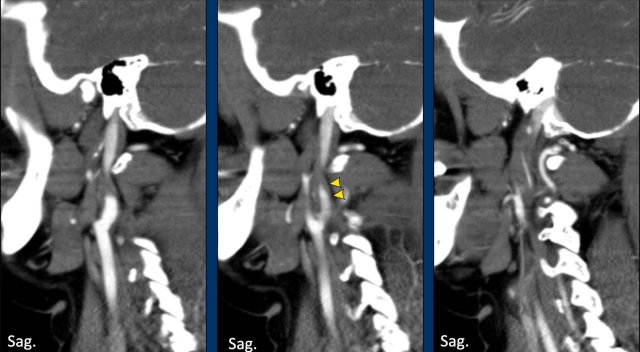

Two cases of a carotid pseudo-occlusion.

In the first case (left) the contrast

stop is rather abrupt, although a small zone of diminishing contrast density can

be seen.

In this case the differentiation between a pseudo-occlusion and a dissection or atherosclerotic occlusion

can be difficult.

However, we do not see the typical flame shape

configuration of the bulbus as seen in a dissection and we see no signs of

atherosclerosis (no plaque or calcifications).

In the second case the gradually

dimishing contrast density is cleary seen over a longer course (arrowheads).

This

is clearly a carotid pseudo-occlusion.